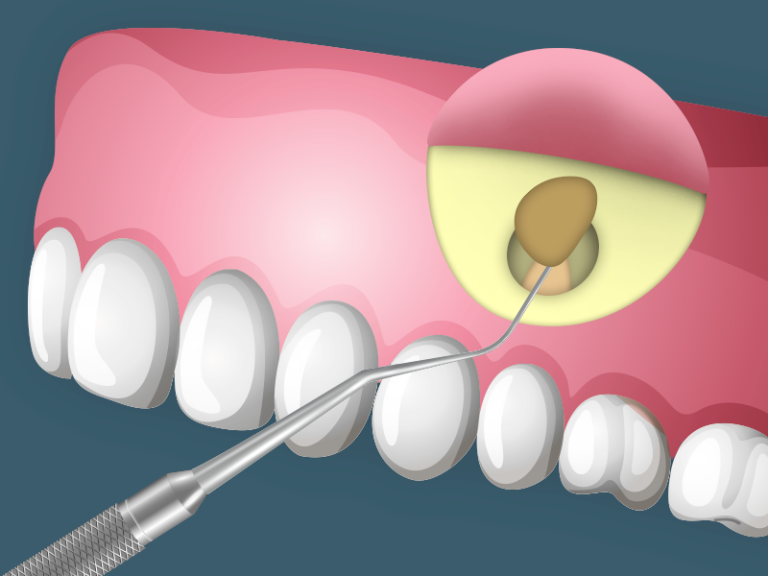

É uma cirurgia que tem por finalidade a remoção da lesão que se forma no ápice (ponta da raiz do dente). Existem dois tipos básicos de cirurgia: uma que apenas remove a lesão através de curetagem e outra que, além disso, remove o ápice da raiz.

Nessa região da raiz, existe um orifício pelo qual passam vasos e nervos que vão nutrir a polpa dentária. Quando a polpa está infectada, a região do ápice também poderá estar infectada e aí se forma um processo inflamatório.